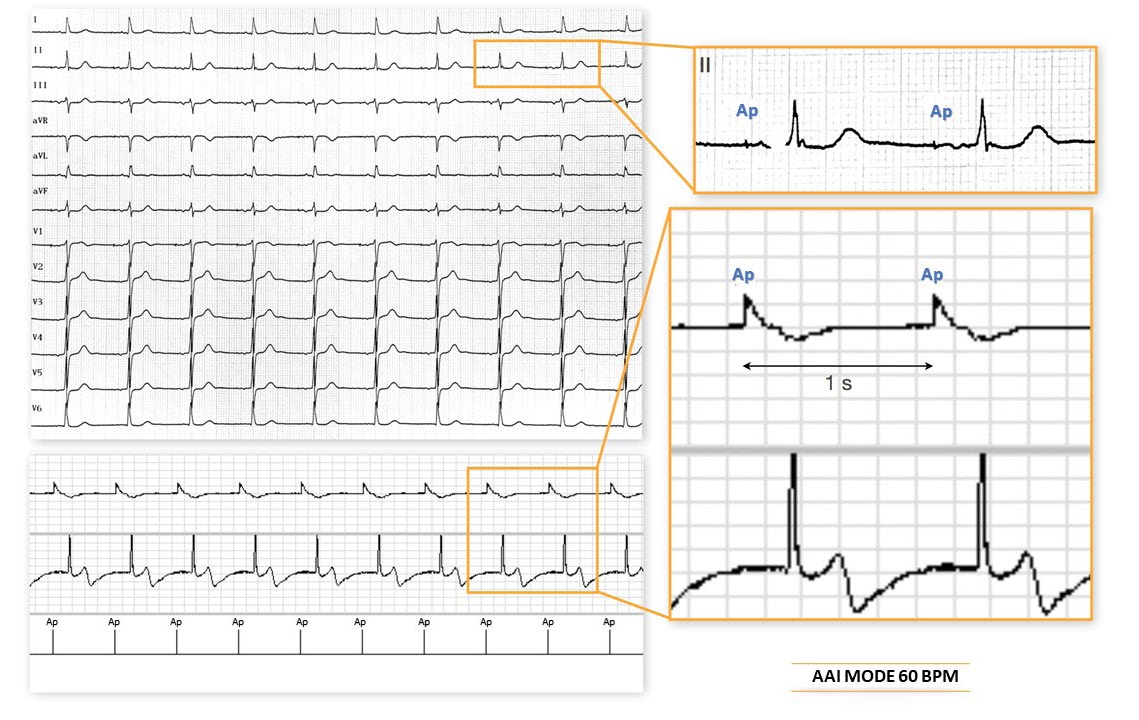

AAI mode 60 beats/minute: atrial pacing at the minimum rate (1 second escape interval) faster than the intrinsic sinus activity; intrinsic atrioventricular conduction;